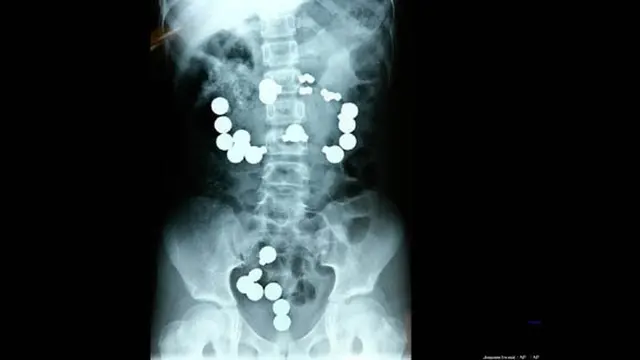

Pria Telan 830 Gram Pil Narkoba

Gambar di atas tampak mengerikan, itu adalah 72 kapsul kokain berukuran besar yang ada di dalam tubuh seorang pria. Semua kapsul itu adalah obat-obatan terlarang dengan berat mencapai 830 gram. Tidak terbayang bagaimana rasanya memiliki tubuh berisi puluhan kapsul seperti gambar di atas.

Gambar ini diambil dari alat pemindai CAT oleh Polisi Federal Brasil. Pada tanggal 16 September 2011, seorang pria muda yang diidentifikasikan sebagai pria Irlandia mencoba naik pesawat di bandara Congonhas di Sao Paulo, Brasil. Agar tidak ketahuan membawa narkoba, pria ini nekat menelan 72 pil. Akibatnya.. dia berurusan dengan polisi dan seperti itulah bagian dalam tubuhnya. Hii..